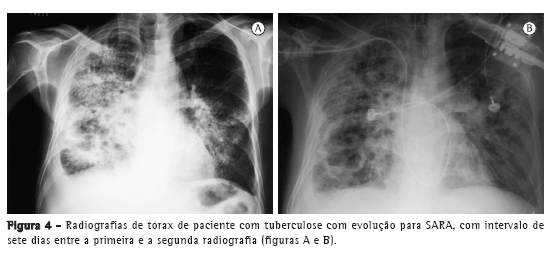

Com relação aos achados radiológicos, infiltrados reticulares e consolidação são os padrões mais frequentes,(5,6,10,15,17) sendo que cavitação pode estar presente em 27-50% dos casos.(6,10,16) As Figuras 1 a 4 mostram alguns dos principais padrões radiológicos nesse contexto.

Os pacientes com tuberculose e necessidade de cuidados intensivos podem evoluir para síndrome da angústia respiratória aguda (SARA). A incidência descrita de SARA é variável: 12,1%,(10) 13,4%,(15) 28,1%(5) e, em alguns estudos, até mais de 60%.(6,16) Em uma série de casos com 15 pacientes hospitalizados com tuberculose e insuficiência respiratória, apesar das características clínicas e radiológicas compatíveis com SARA, os achados histopatológicos foram compatíveis com broncopneumonia tuberculosa, sem evidência de SARA.(7) Em um estudo no Brasil, as alterações histopatológicas pulmonares encontradas em autopsias de pacientes que evoluíram a óbito por insuficiência respiratória aguda foram revisadas, e o principal padrão associado com tuberculose foi o dano alveolar difuso.(11)